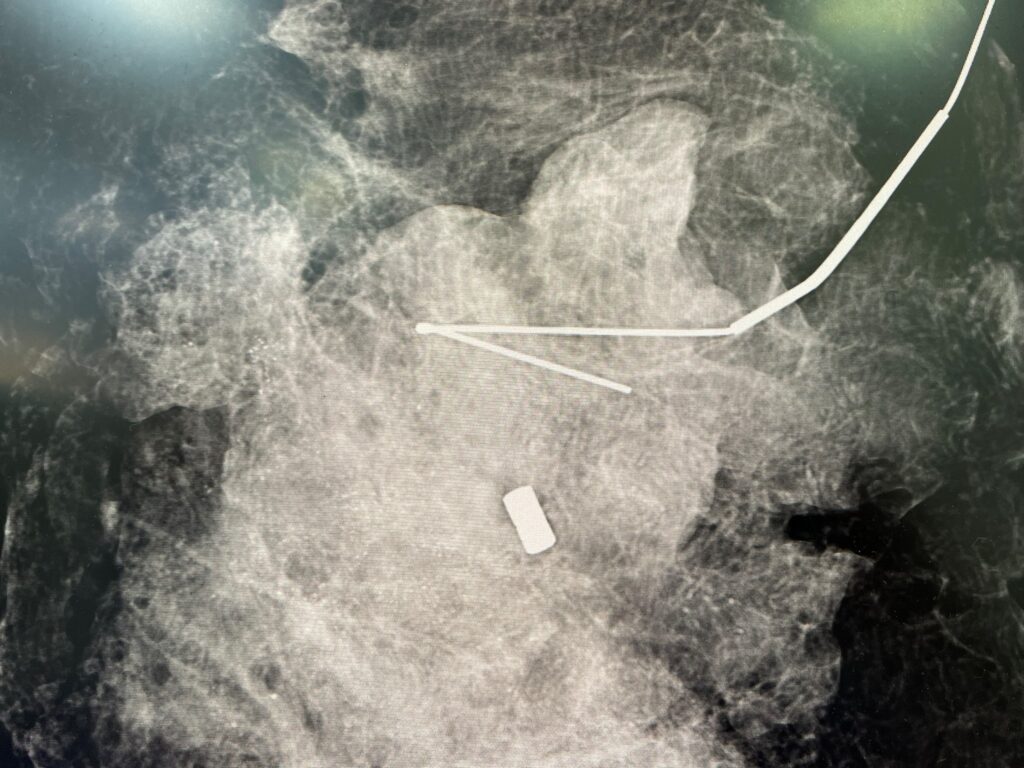

Atualmente alguns hospitais do Rio de Janeiro possuem o aparelho para visualização pela radiologia da peça cirúrgica (figura 7) dentro do centro cirúrgico.

Figura 7: Radiografia da peça cirúrgica com clipe